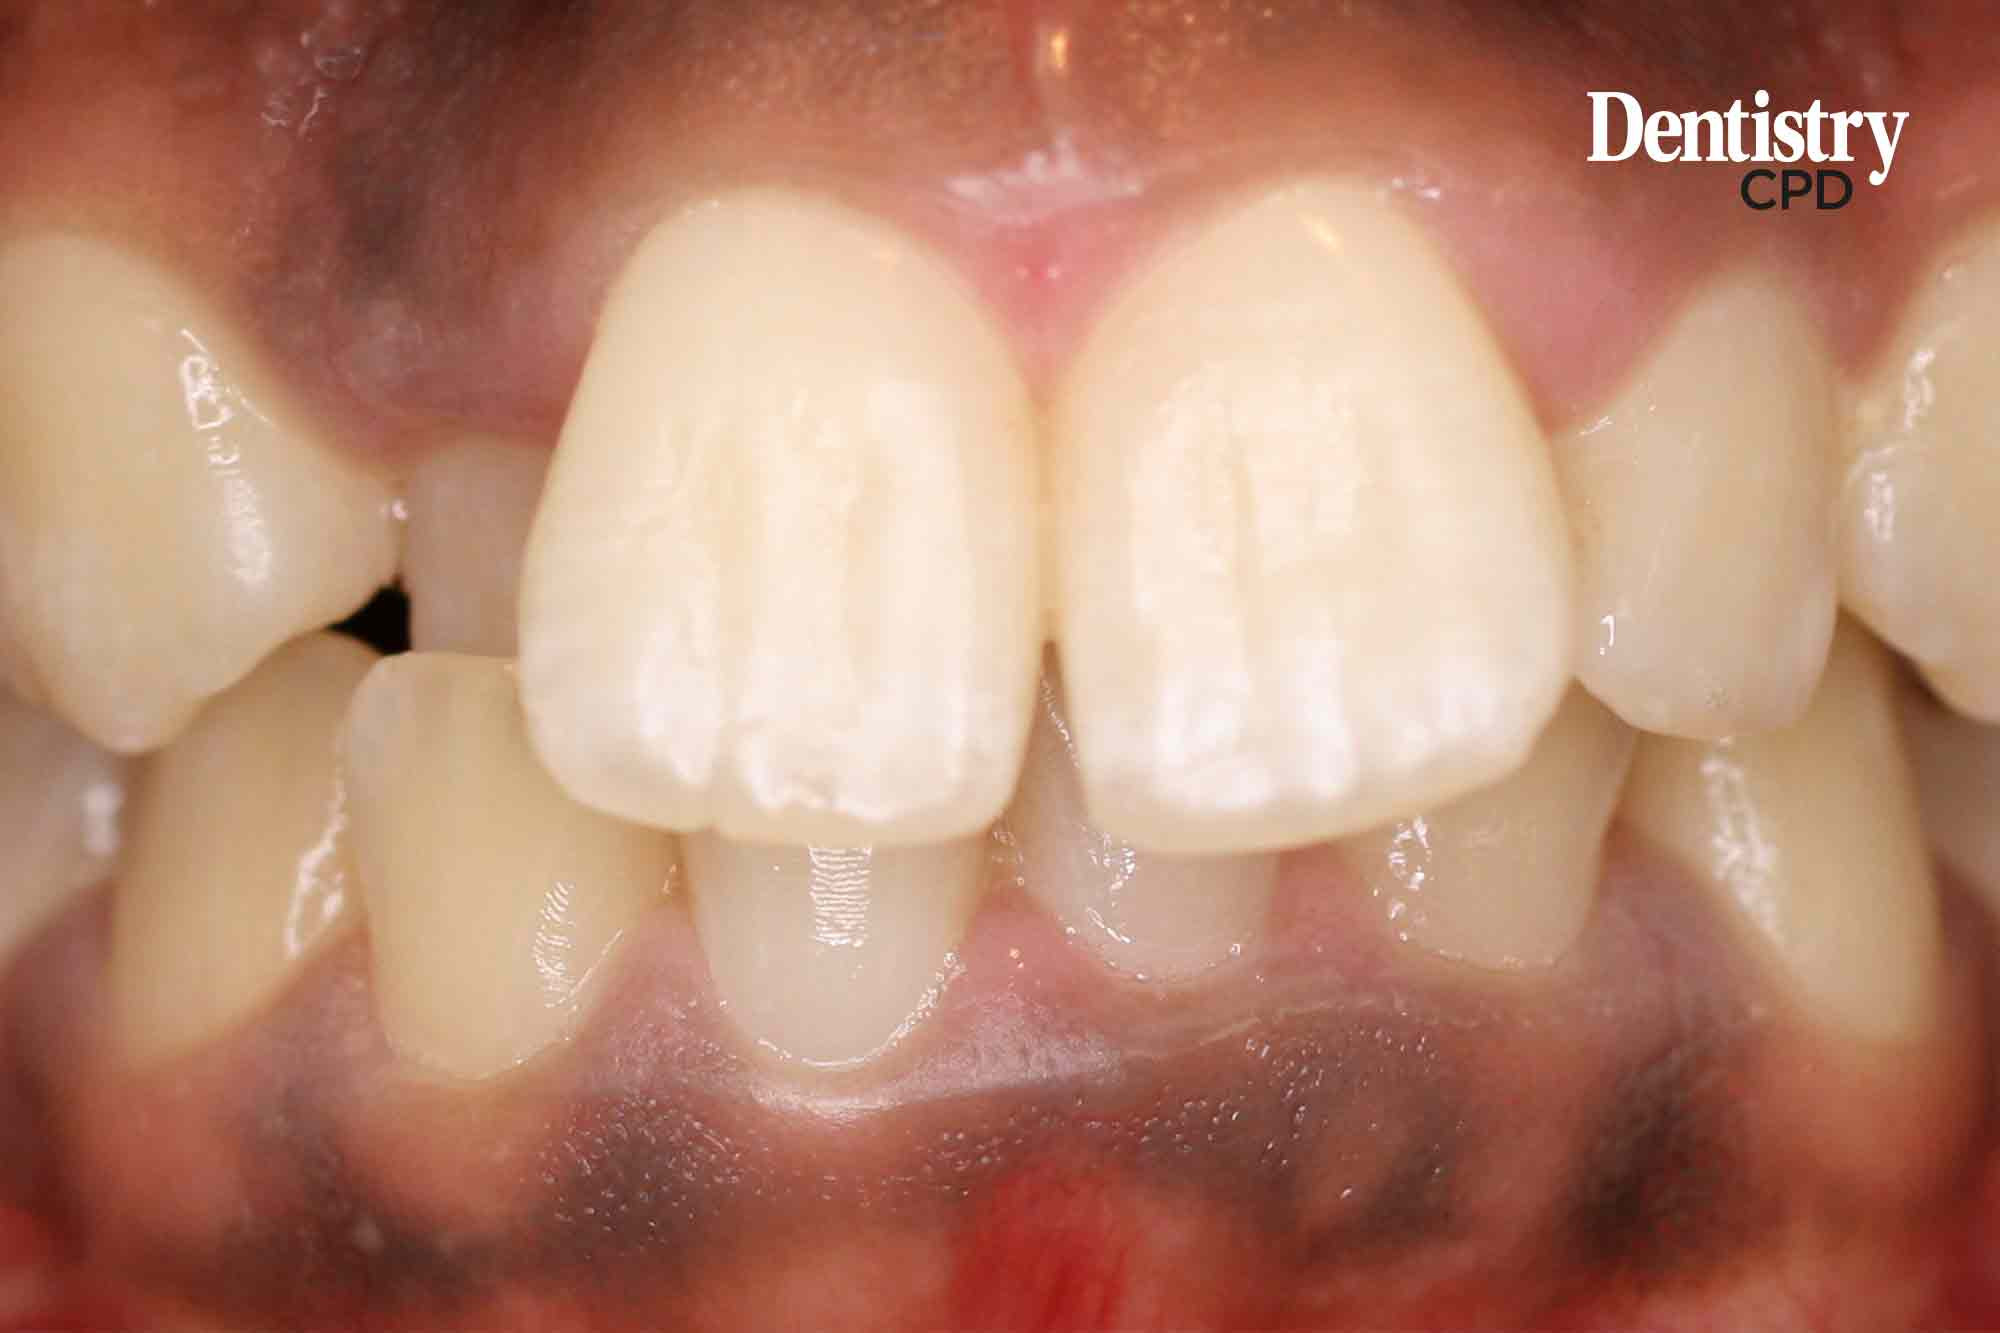

Dr Runa Mowla-Copley presents a case with a high-angle class II division 1 malocclusion treated on a non-extraction basis.

To show diagnosis and treatment planning for treating a high-angle class II division 1 malocclusion